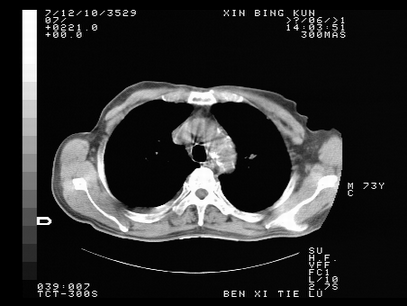

标题: CT10820:男,73岁,病史肺TB,现病史肺炎,直肠CA术后 [打印本页]

双肺间质改变,依据病史双肺多发结节灶考虑转移,少量胸水.

1.两肺结核.2.两肺多发转移瘤.3右侧少量胸腔积液4.主动脉钙化.

双肺多发结节及条片状致密影,右侧少量胸腔积液。临床:直肠ca术后,肺tb病史。综合考虑:1 双肺转移!2 继发性肺结核合并感染!

此人病史较复杂,原有肺结核,直肠癌术后。肺部病灶形态亦呈多形性。因此,不可仅以一种病来解释肺部的病变。双肺多发的类圆形结节灶,结合病史还是首先考虑转移瘤,而双肺其余病灶还需结合化验室检查,结核或肺部感染在无其它检查资料的情况下不好排除。还是那句话----放射科医生不是开照像馆的,我们也是医生,看片一定要多结合临床及其它检查资料。要当一名合格的放射科医生,并不比当一名临床医生容易,我们可别把自已不当医生看。

两肺多发结节影,并见滋养动脉与其相连,考虑 两肺转移. 右侧胸腔积液考虑胸膜转移.

左肺上叶下叶背段,右肺中下叶见多发斑片状、条索状高密度影,兵变周围小结节影形成“树芽”样改变。 左肺上叶舌段近前胸壁处及右肺中叶内侧段见结节影。右侧胸膜腔内见液体密度区。纵隔内未见明确增大淋巴结。考虑左肺上叶舌段近前胸壁处及右肺中叶转移瘤可能性大。两肺继发型肺结核。右侧胸腔积液。

还有心包少量积液。